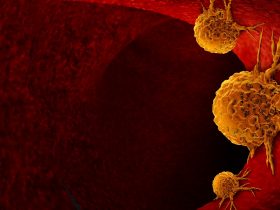

The long non-coding RNA metastasis-associated lung adenocarcinoma transcript-1 (MALAT1) was initially found to be overexpressed in early non-small cell lung cancer (NSCLC). Accumulating studies have shown that MALAT1 is overexpressed in the tissue or serum of NSCLC and plays a key role in its occurrence and development. In addition, the expression level of MALAT1 is significantly related to the tumor size, stage, metastasis, and distant invasion of NSCLC. Therefore, MALAT1 could be used as a biomarker for the early diagnosis, severity assessment, or prognosis evaluation of NSCLC patients. This review describes the basic properties and biological functions of MALAT1, focuses on the specific molecular mechanism of MALAT1 as a microRNA sponge in the occurrence and development of NSCLC in recent years, and emphasizes the application and potential prospect of MALAT1 in molecular biological markers and targeted therapy of NSCLC.